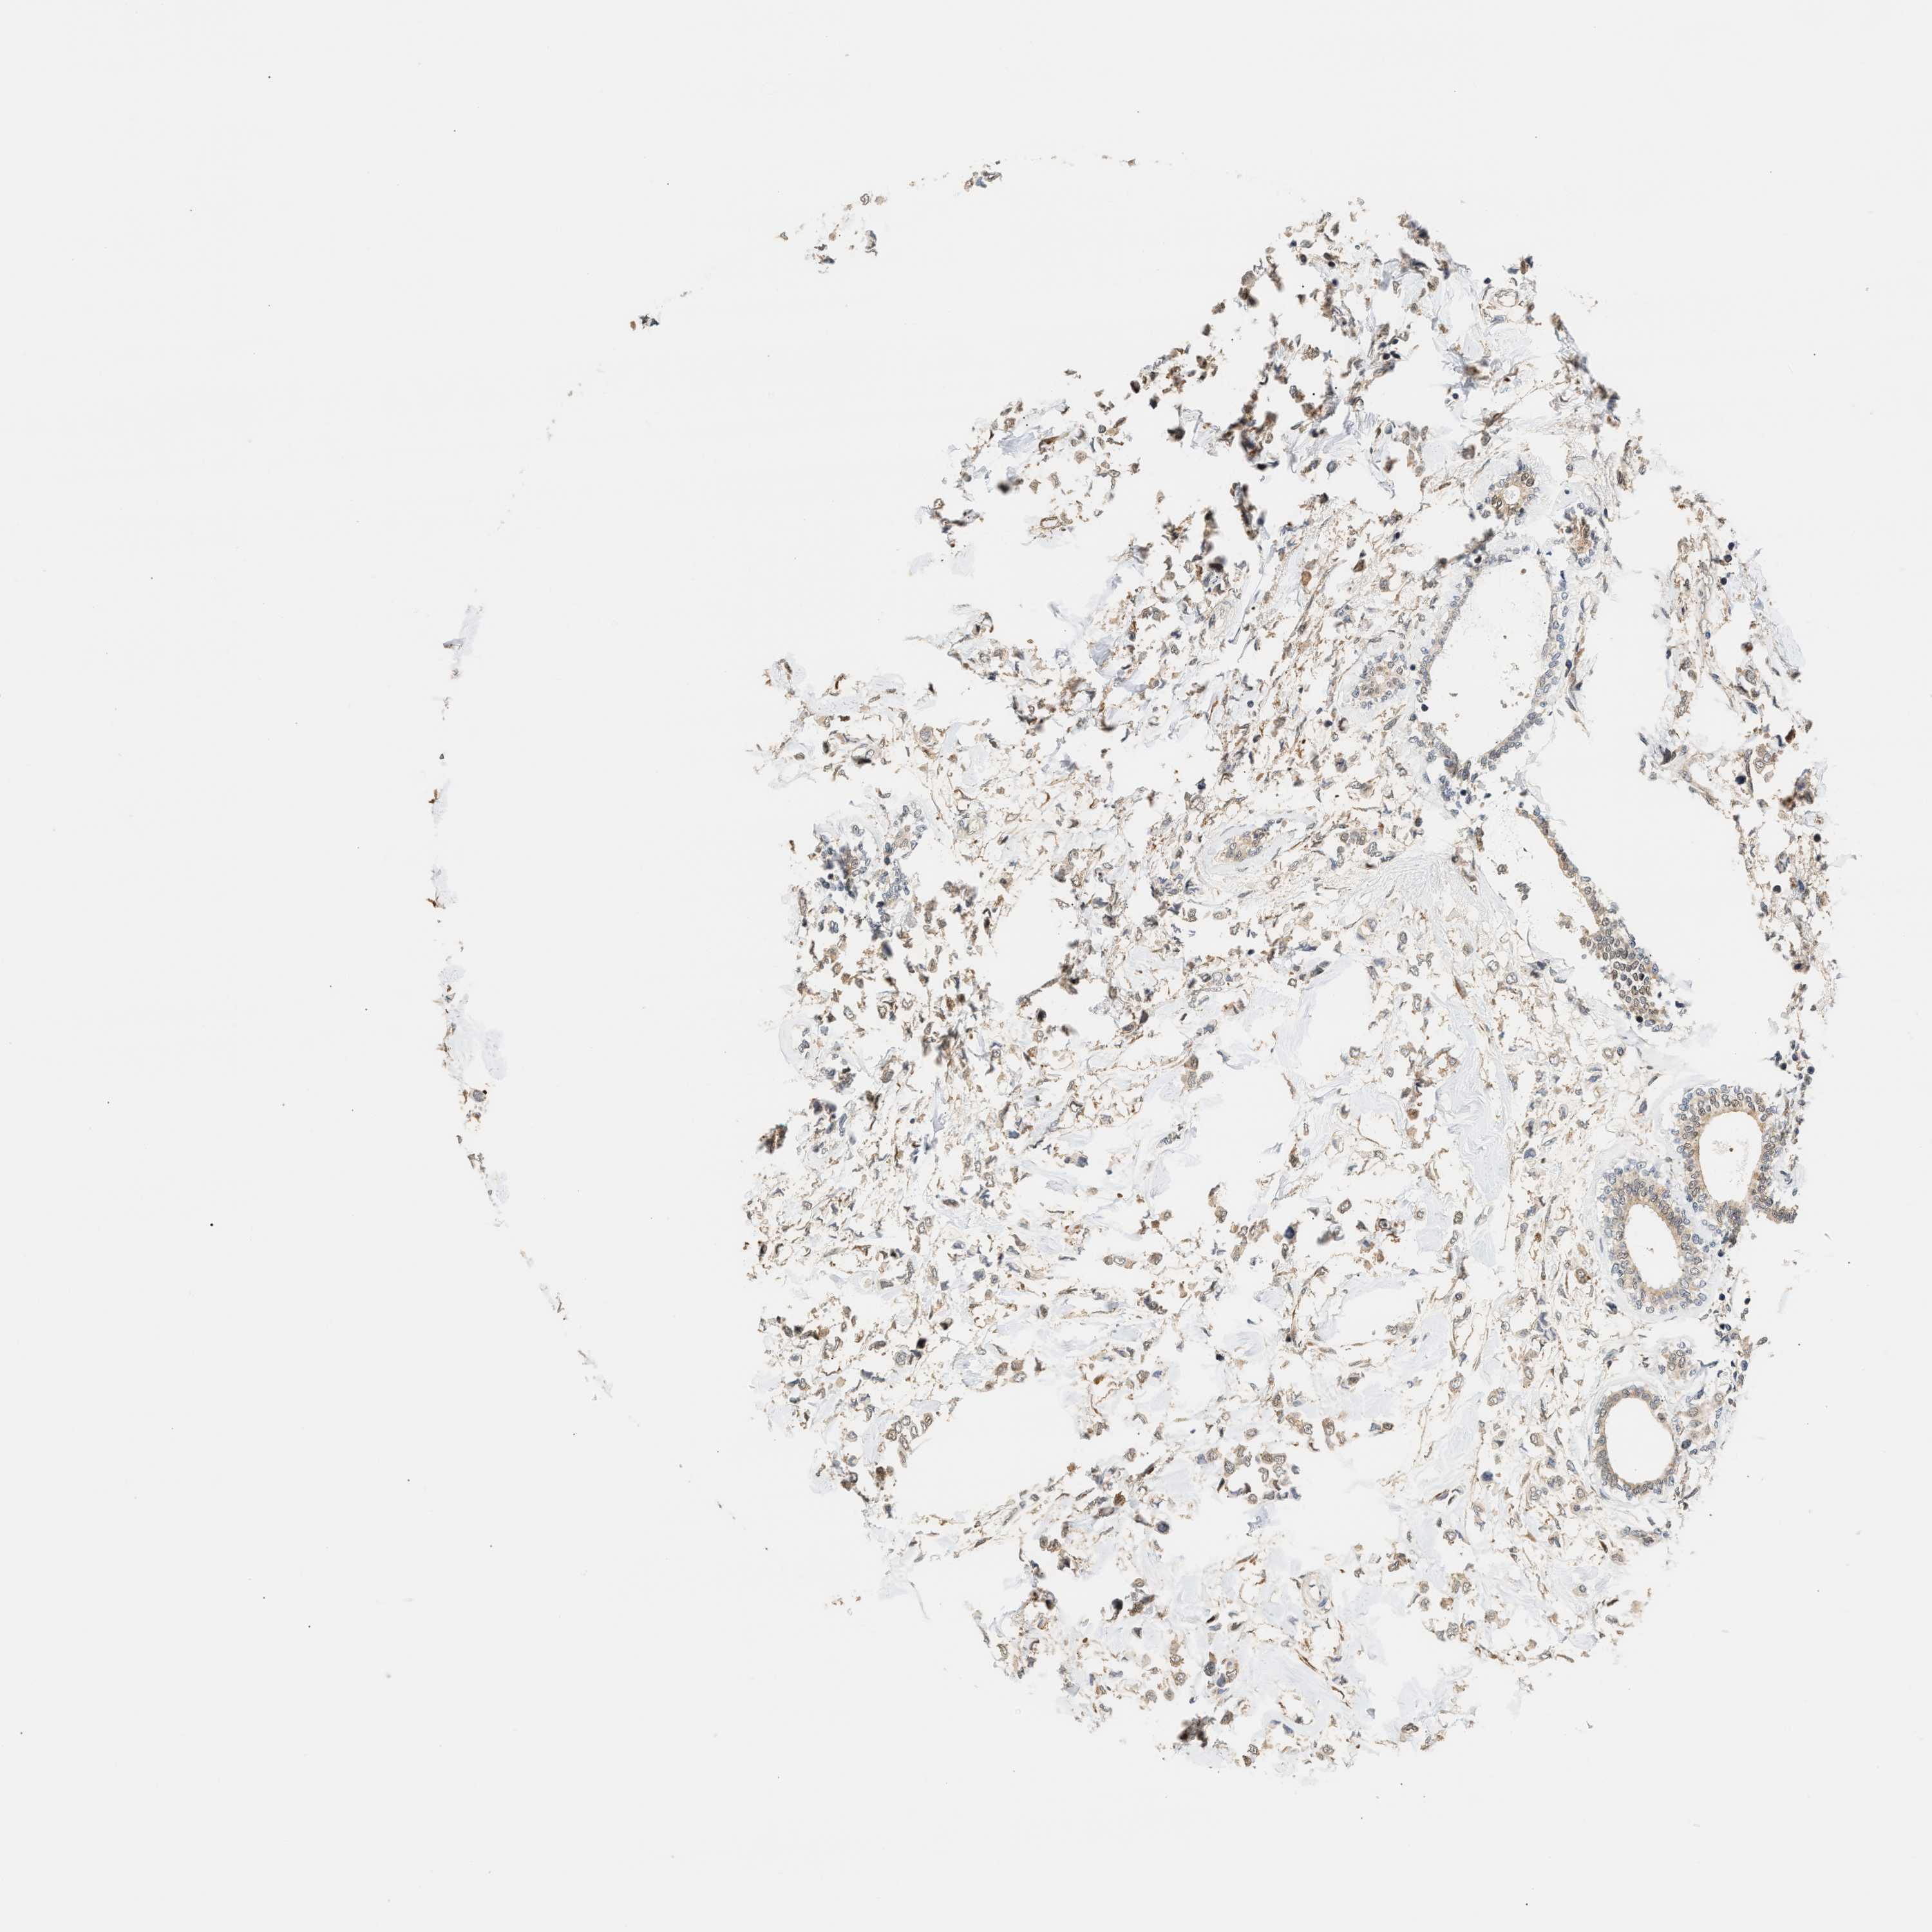

CANCER BREAST CANCER Show tissue menu

BRCA TCGA BRCA VALIDATION PROTEIN EXPRESSION

Breast cancer

Human cancer